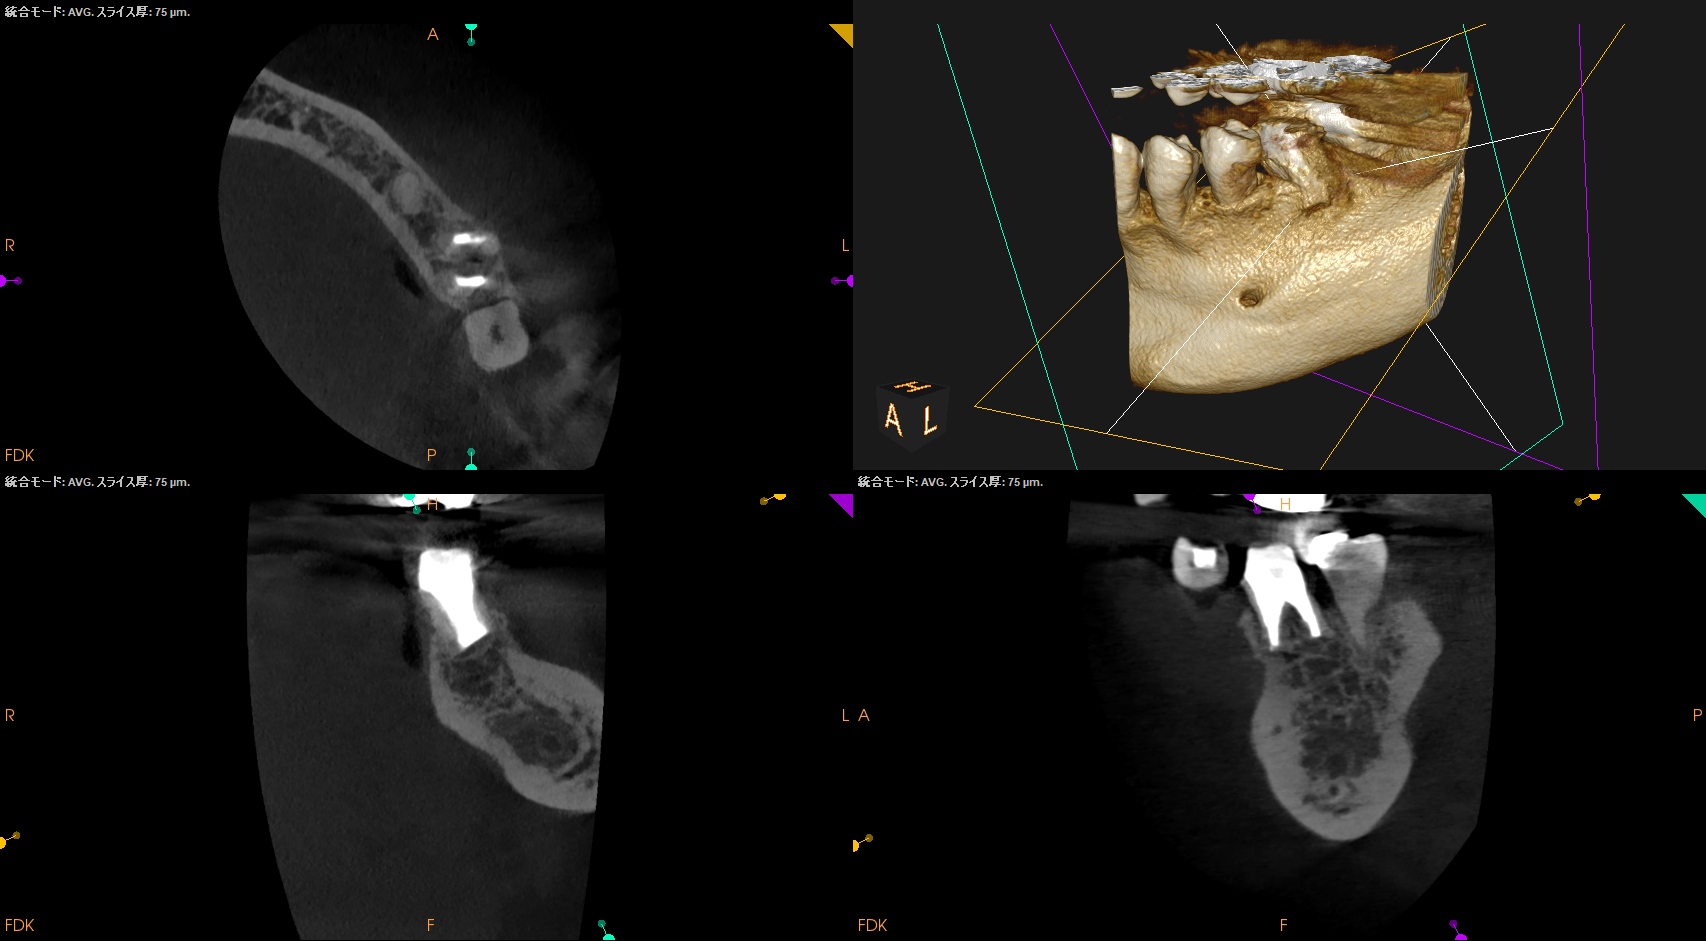

CBCT(2024.9.12)

MB

ML

D

術後にPA, CBCTを撮影した。

M

問題はないだろう。

以下のようにPA,CBCTはなった。